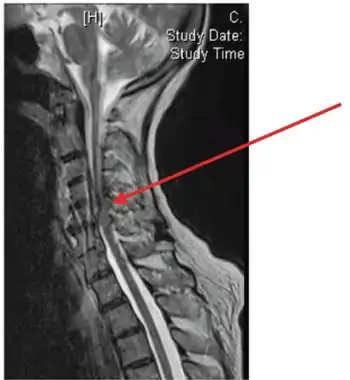

Image showing epidural abscess (and cord compression)

An epidural abscess refers to a collection of pus and infectious material located in the epidural space superficial to the dura mater which surrounds the central nervous system. Due to its location adjacent to brain or spinal cord, epidural abscesses have the potential to cause weakness, pain, and paralysis.

A spinal epidural abscess (SEA) is a collection of pus or inflammatory granulation between the dura mater and the vertebral column.[1] Currently the annual incidence rate of SEAs is estimated to be 2.5-3 per 10,000 hospital admissions. Incidence of SEA is on the rise, due to factors such as an aging population, increase in use of invasive spinal instrumentation, growing number of patients with risk factors such as diabetes and intravenous drug use.[1] SEAs are more common in posterior than anterior areas,[2] and the most common location is the thoracolumbar area, where epidural space is larger and contains more fat tissue.[3] SEAs are more common in males, and can occur in all ages, although highest prevalence is during the fifth and seventh decades of life.[1]